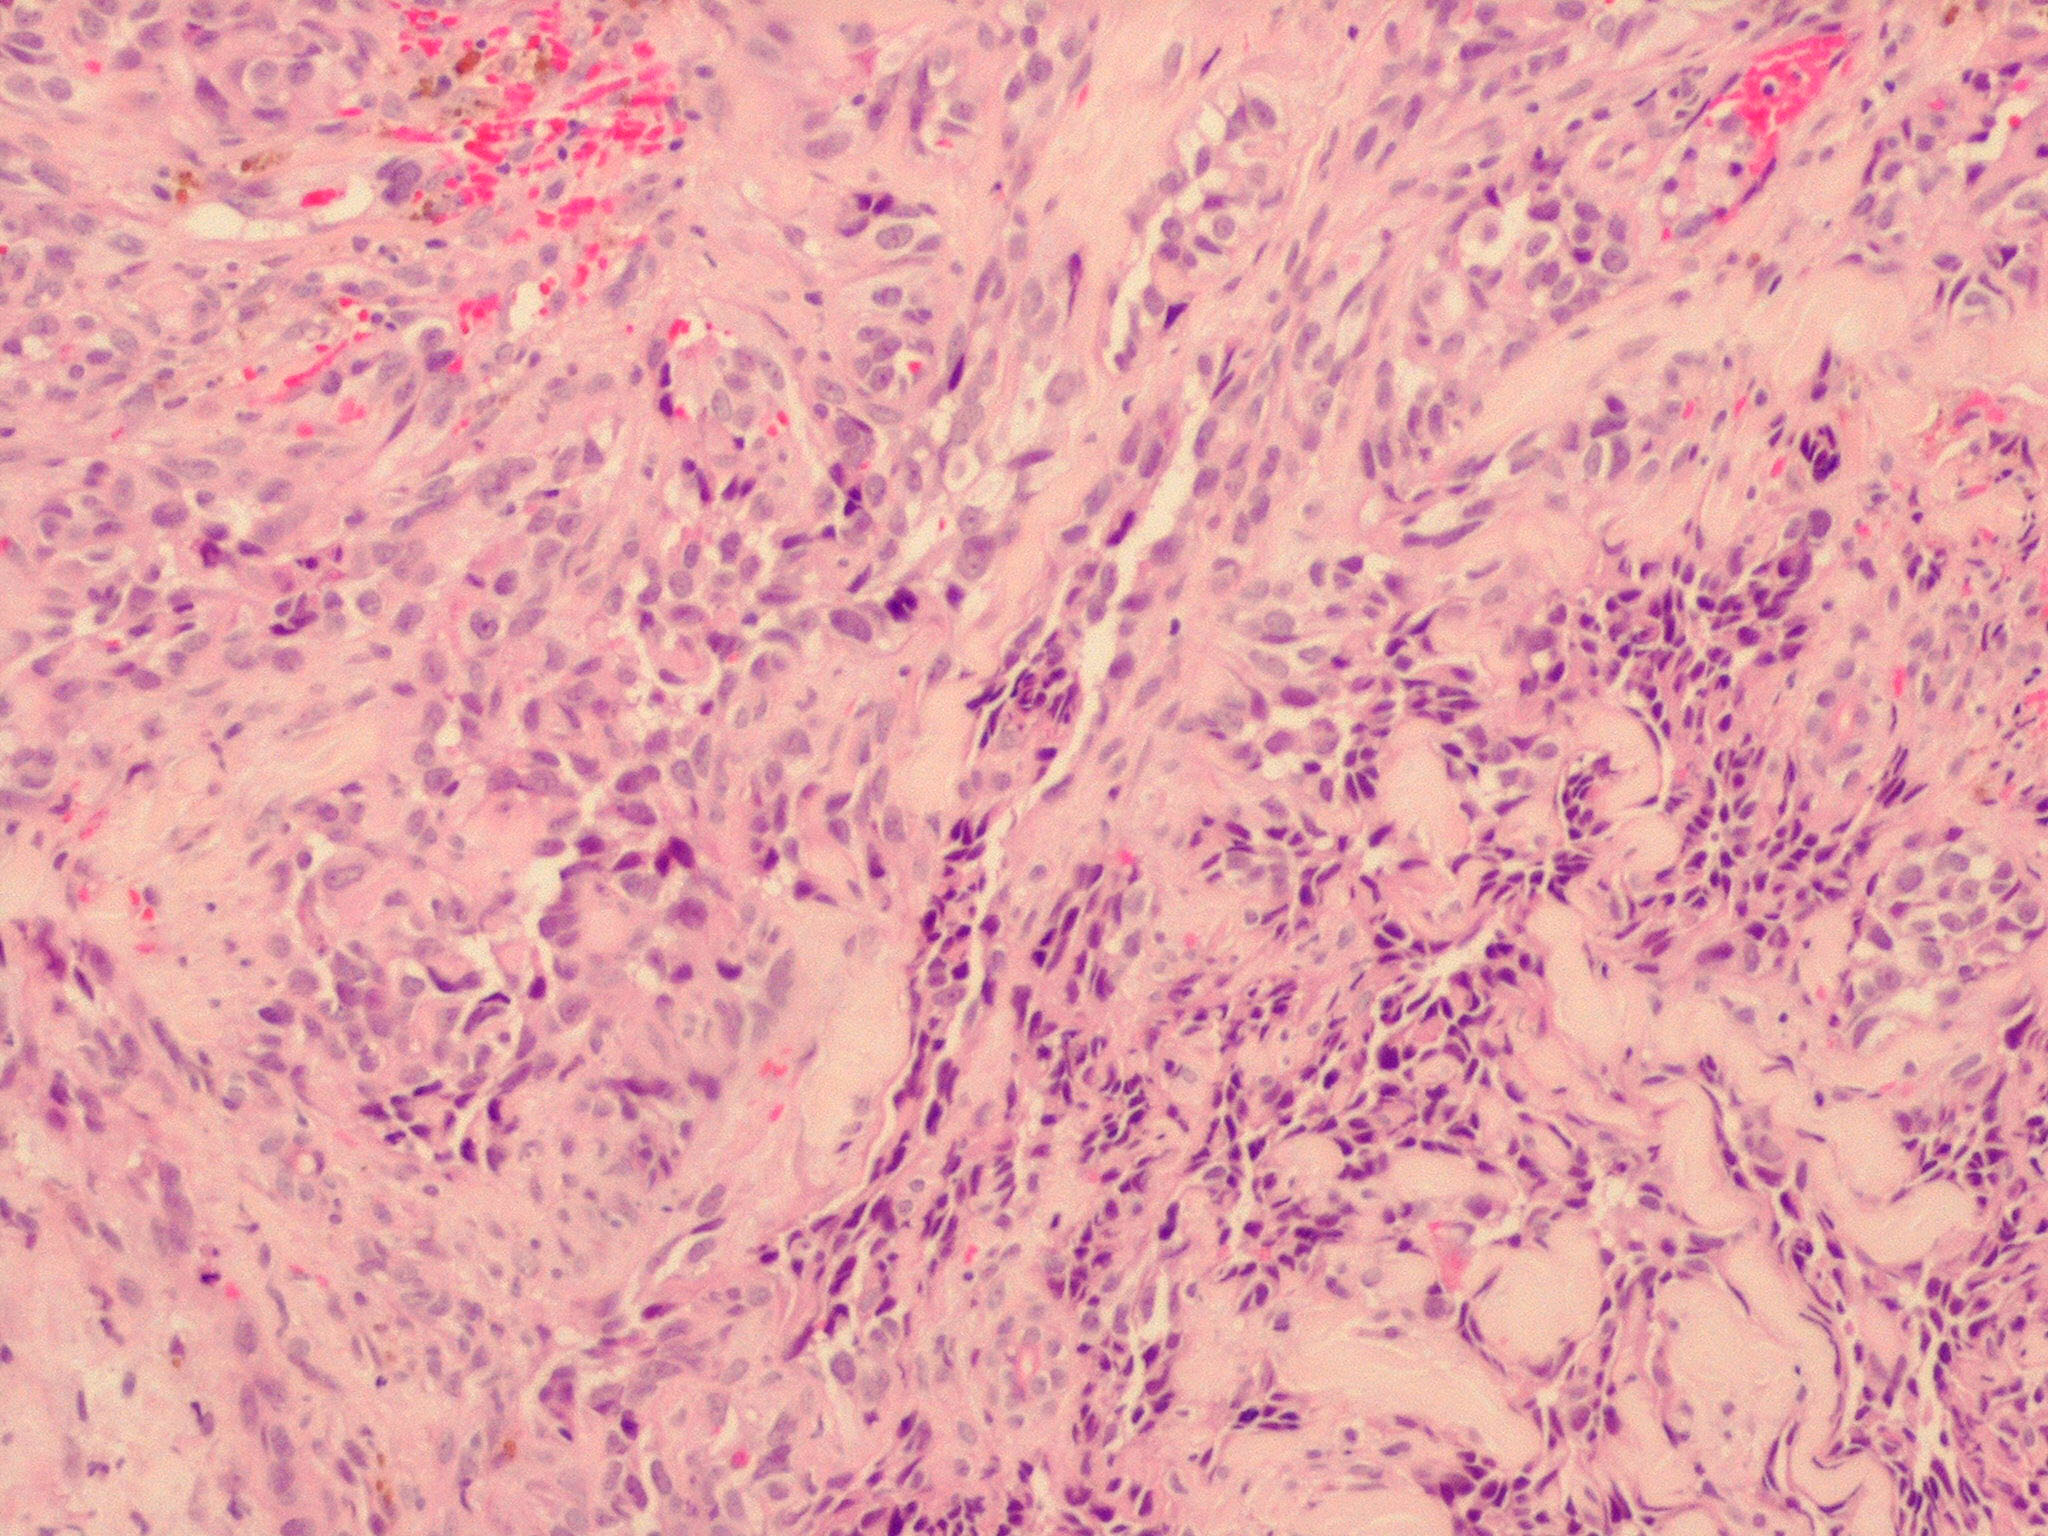

Angiosarcoma = الساركوم الوعائي